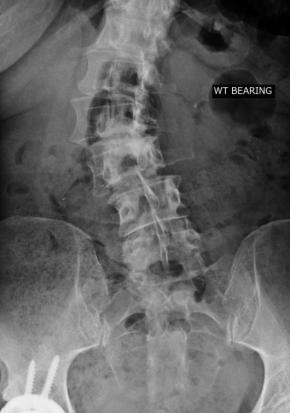

I hit the trifecta with Dr. Lowe, a gifted surgeon in his prime. His knife skills are out of this world. He was the 9th orthopedic surgeon I consulted and the first one who said he could fix my back. He fixed my back, he fixed my husband's paratrooper back and then he fixed my "inoperable" neck!

I was referred to him by a neurosurgeon, by the way. Neurosurgeon wouldn't touch my neck. Dr. Lowe didn't hesitate. This doctor is a Godsend.